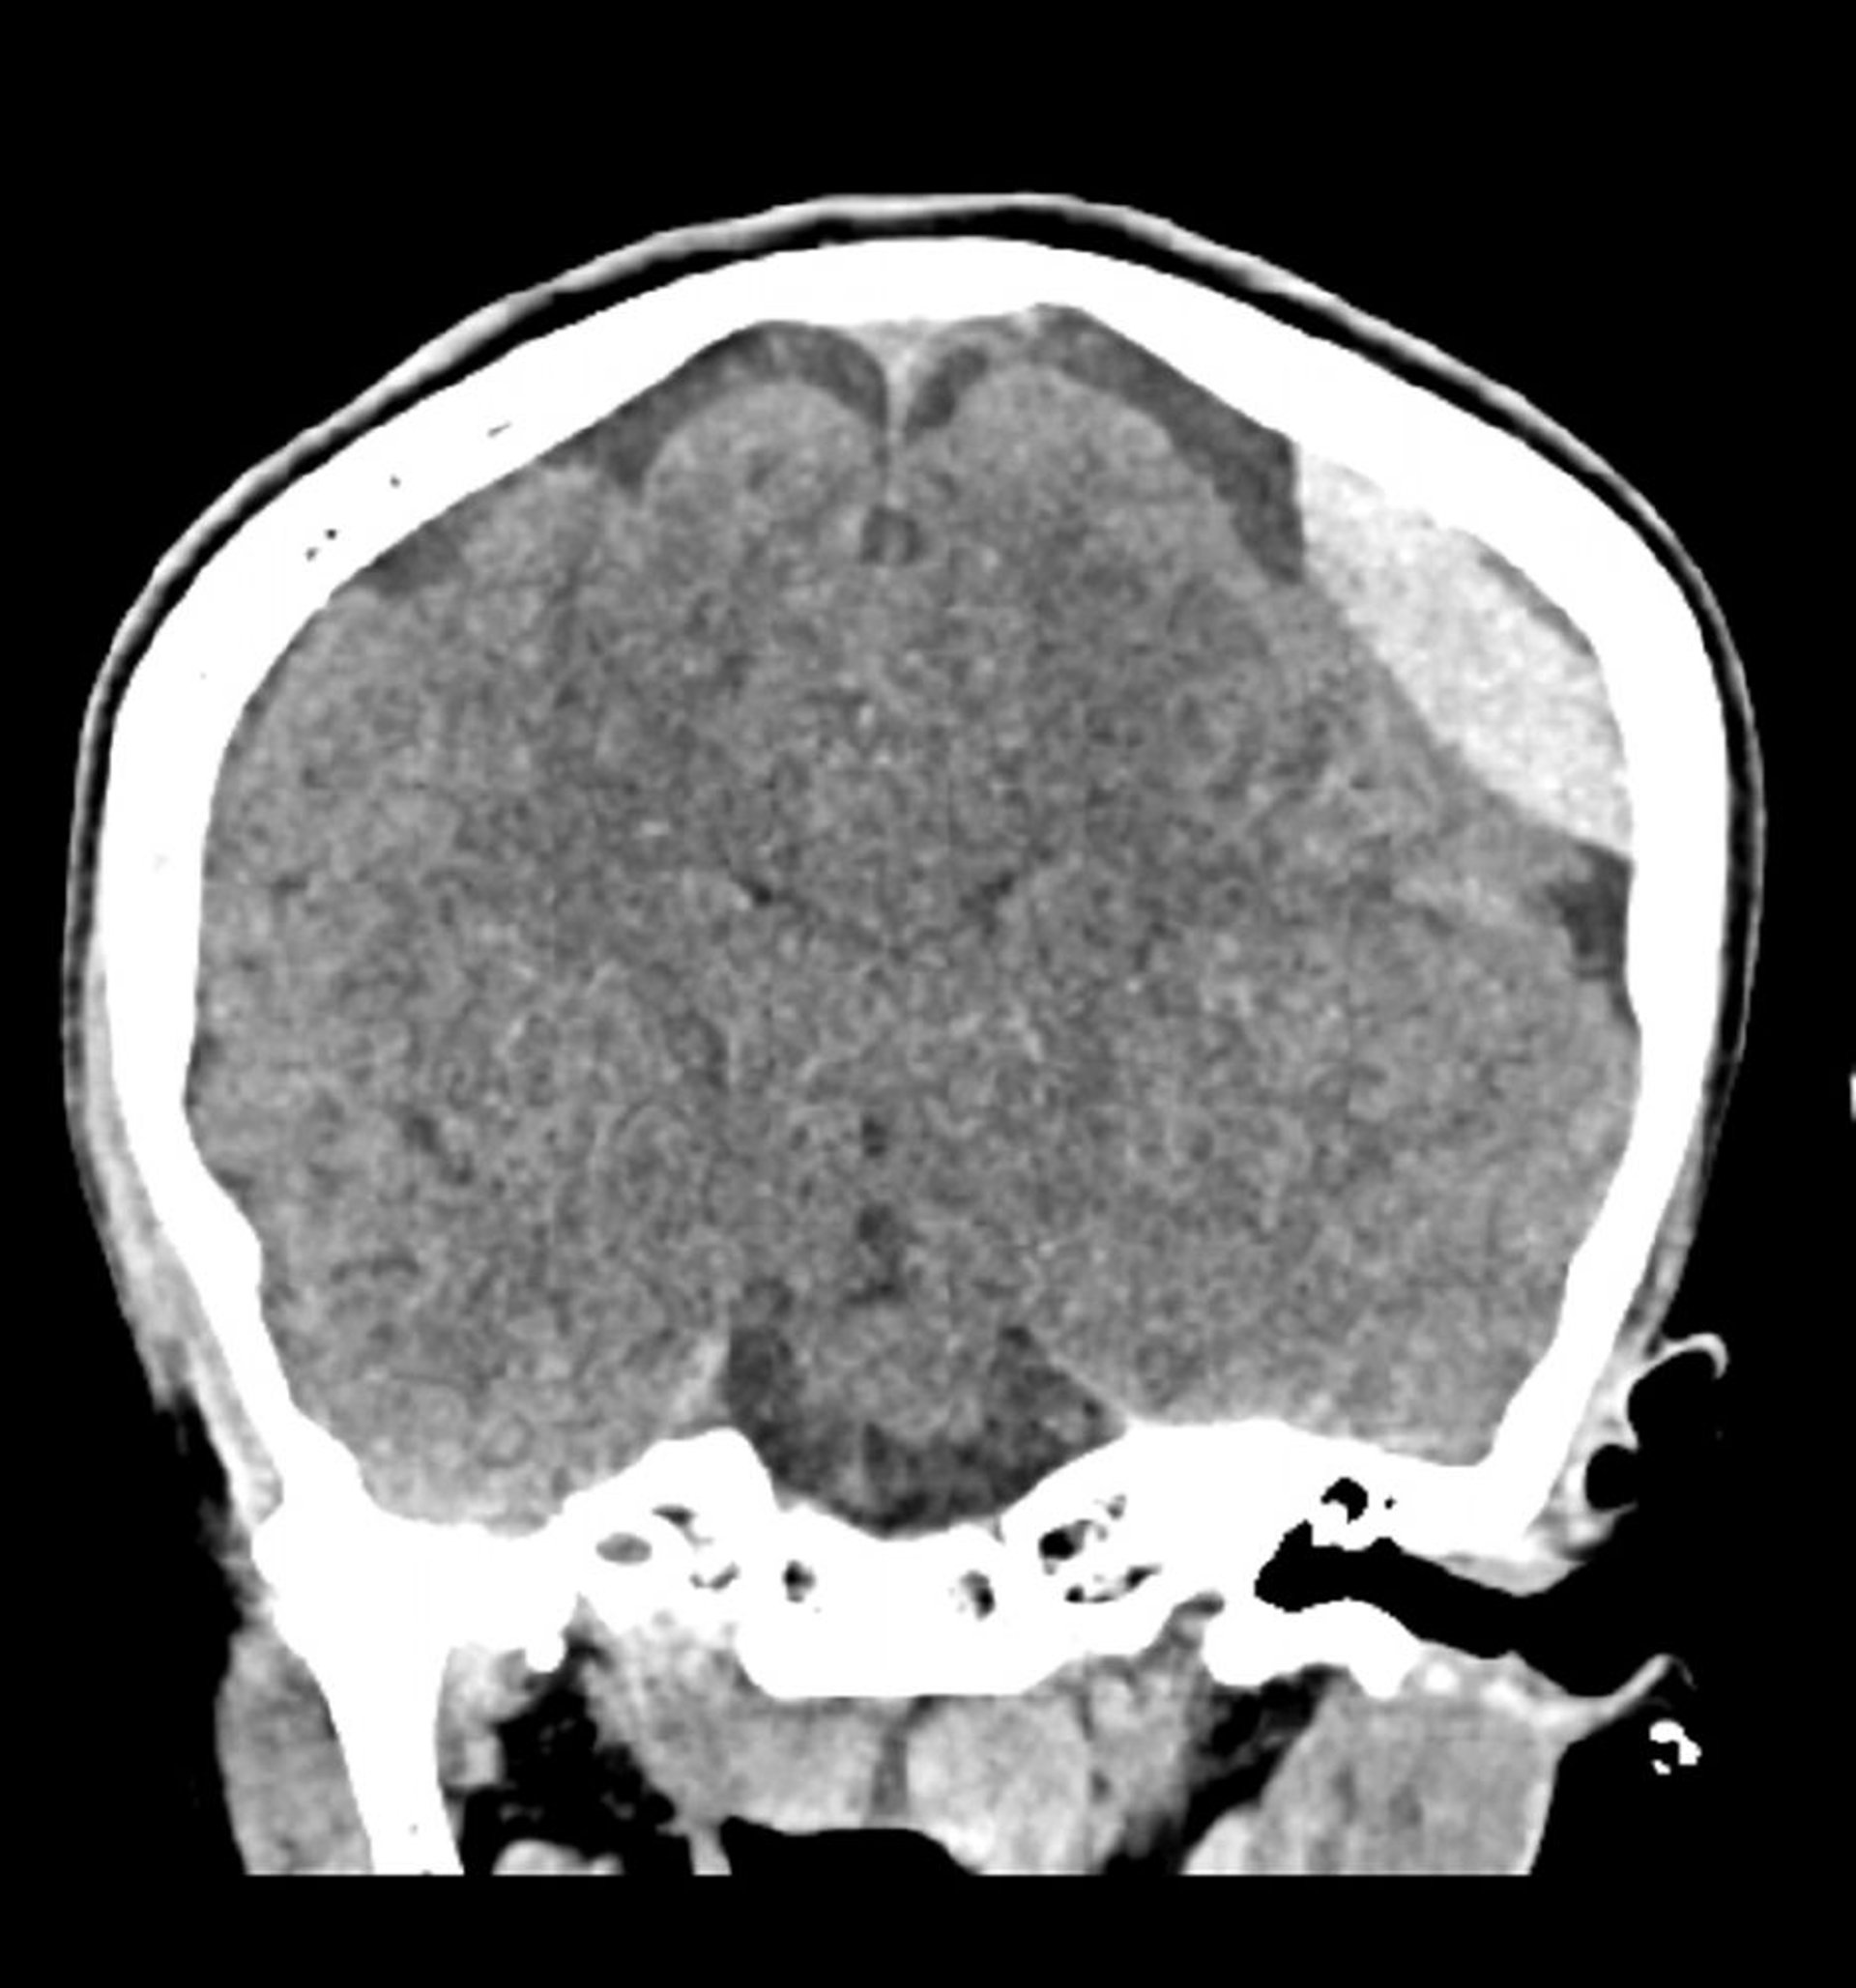

Hemorragia epidural (TC coronal)

Hiperdensidade lentiforme clássica (em forma de lente) que não ultrapassam as linhas de sutura.